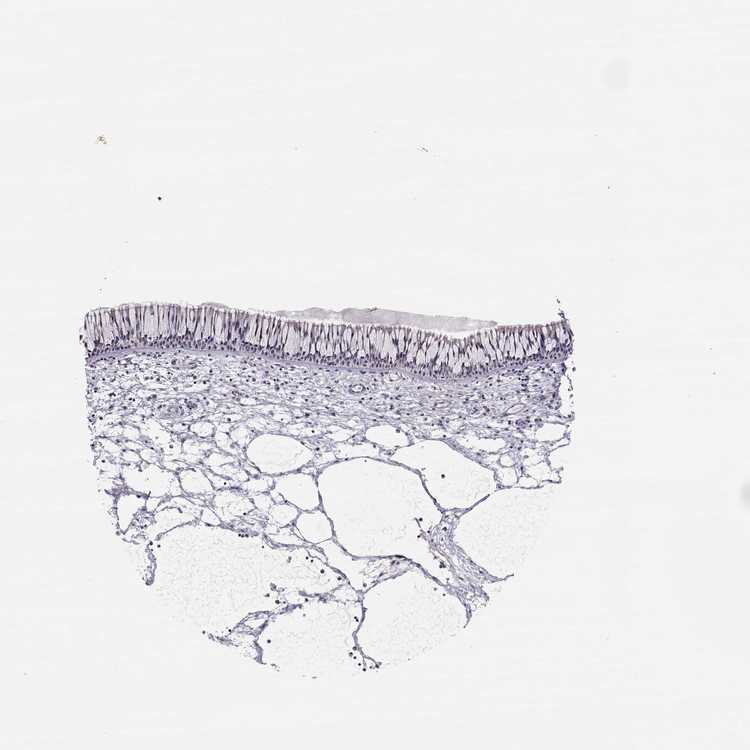

TISSUE PRIMARY DATA NASOPHARYNX Show tissue menu

NASOPHARYNX - Antibody stainingi

Antibody staining in the annotated cell types in the current human tissue is reported as not detected, low, medium, or high, based on conventional immunohistochemistry profiling in selected tissues. This score is based on the combination of the staining intensity and fraction of stained cells.

Each image is clickable and will lead to virtual microscopy that enables deeper exploration of all samples and also displays staining intensity scores, fraction scores and subcellular localization as well as patient and tissue information for each sample.

Antibody HPA073031

Respiratory epithelial cells Not detected